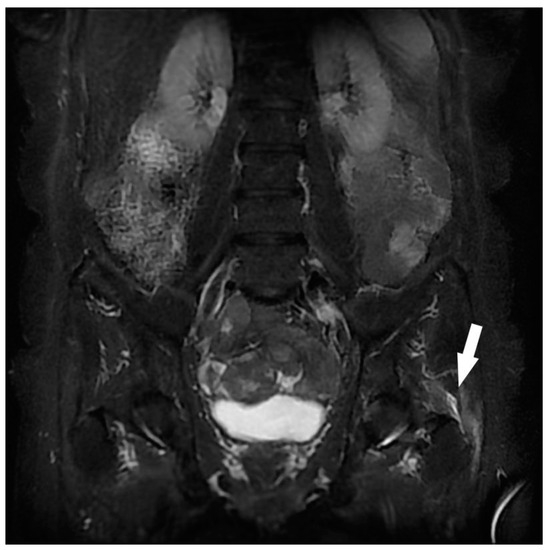

| Gluteal Muscles | Gluteal tendinobursitis | 21 |

| Musculotendinous | Gluteal tendinobursitis 2 | 10 |

| Proximal iliotibial band enthesopathy 2 | 1 | |